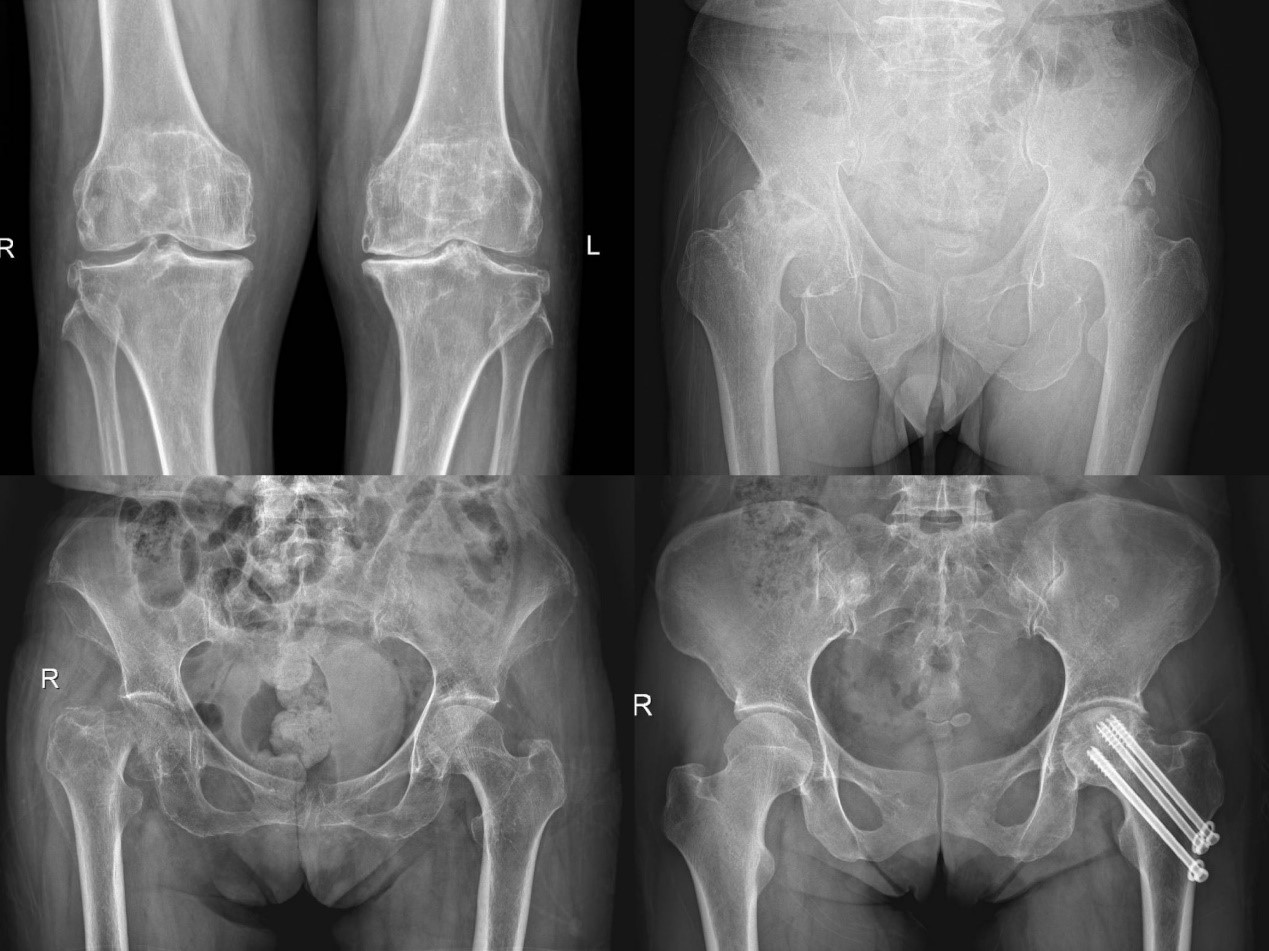

人工关节置换手术是治疗退行性骨关节炎、类风湿关节炎、痛风性关节炎、创伤性关节炎、股骨头坏死、髋关节发育不良等关节疾病及畸形的有效手段,能够快速、有效的恢复患者关节活动功能,很大程度上提高了患者的生活质量,免受长年累月疼痛的困扰。

骨关节外科主任李广恒教授表示,国家集中采购人工关节之前,人工关节假体价格高昂,很多患者因为经济原因无法接受人工关节置换的治疗,对普通工薪家庭来说压力属实不小。现在国家集采后,价格大幅度下降,减轻了不少患者的经济负担,不少患者听说降价后,纷纷前来就医治疗。